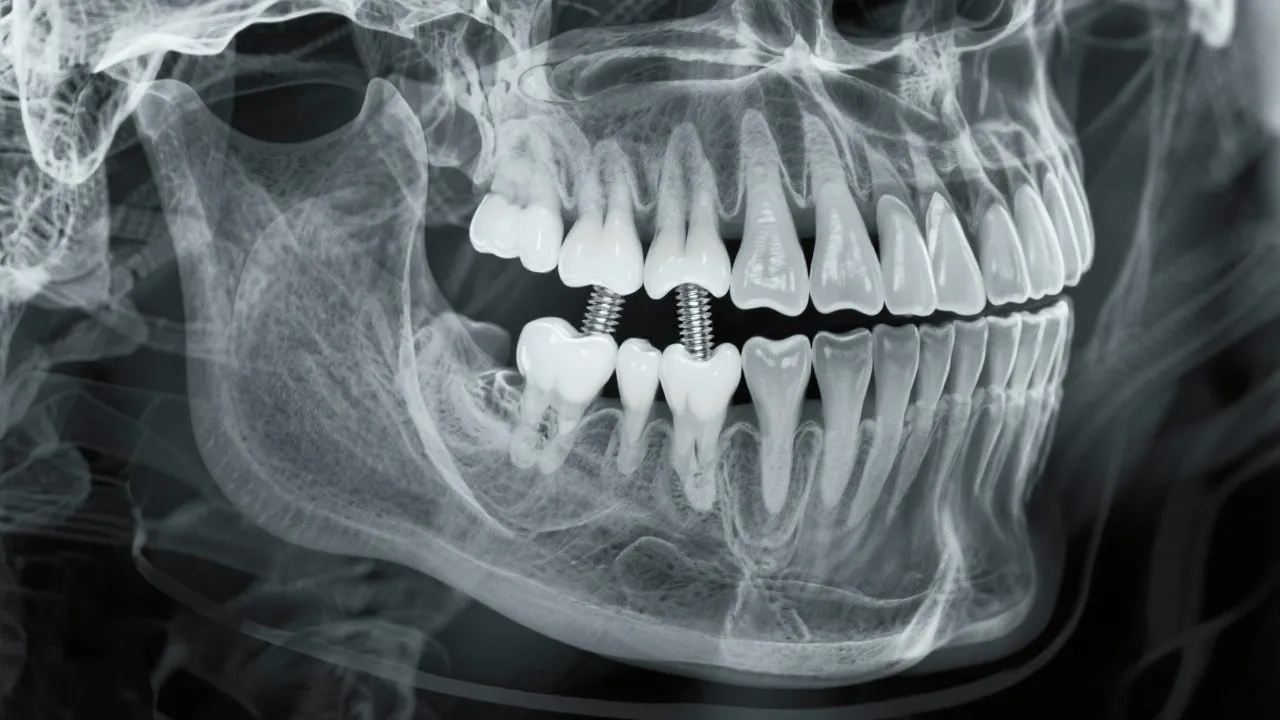

Bone density is a critical factor when considering dental implants. It refers to the amount of bone material present in a specific volume of bone, which directly impacts an implant's stability and longevity. Adequate bone density ensures that the dental implant can support the forces of chewing and other oral functions. Inadequate bone density, however, may lead to complications, affecting the implant's success rate. High bone density provides a stronger anchorage point, which is essential for the integration of the implant within the jawbone. When evaluating candidates for dental implants, dentists often conduct imaging studies like X-rays or CT scans to assessbone density patterns and bone structure.

The process of osseointegration, where the implant fuses with the bone, is heavily dependent on bone quality. Denser bone provides better support and integration for the implant. When bone density is insufficient, additional procedures such as bone grafting may be necessary to enhance bone volume and strength, allowing for a successful implantation process. Each step of the osseointegration process is crucial and requires careful monitoring. We must remember that bone health is not entirely static; it can fluctuate based on lifestyle choices, hormonal changes, or medical conditions. Therefore, maintaining a strong and healthy jawbone is vital not only before receiving implants but also as an ongoing health measure.

Successful dental implantation requires not only the technical skill of the dental surgeon but also the biological readiness of the patient’s jawbone. High bone density provides a solid foundation for implants, reducing the likelihood of structural failure. Despite the importance of bone density, many patients may be deterred by recommendations for additional procedures like grafting. Understanding how these interventions can lead to better long-term results is essential for informed decision-making.

In cases where bone density is questionable, preemptive measures such as bone grafting or the use of mini implants may be considered. Mini implants, which are narrower in design, can sometimes be placed without extensive grafting procedures; however, they may not be suitable for all patients or types of restorations. Collaborating closely with your dental team can help to devise the best approach tailored to your specific situation.